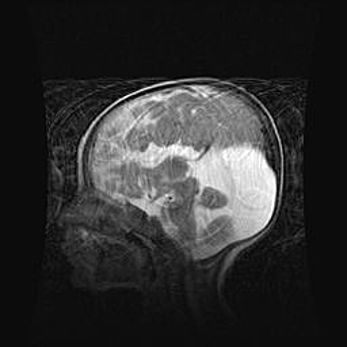

Аномалия Денди-Уокера. Признаки гипоплазии мозолистого тела.

Возраст: 5 месяцев 3 дня

Вес: 5550 г

Пол: мужской

Окружность головы: 39 см

Срок гестации: 40 недель

Аномалия Денди-Уокера – это порок развития головного мозга, для которого характерна триада симптомов: гипотрофия или аплазия червя мозжечка и/или полушарий мозжечка, расширение четвёртого желудочка с формированием ликворной кисты задней черепной ямки, гипертензионная гидроцефалия различной степени.

Гипоплазия мозолистого тела относится к дефектам внутриутробного этапа развития мозговой ткани, возникающим в процессе закладки структур головного мозга, что происходит на начальных этапах развития эмбриона.